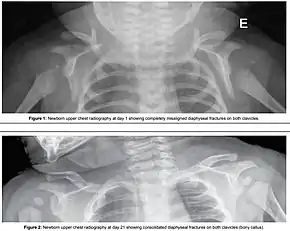

Shoulder dystocia is when, after vaginal delivery of the head, the baby's anterior shoulder gets caught above the mother's pubic bone.[3][1] Signs include retraction of the baby's head back into the vagina, known as "turtle sign".[1] Complications for the baby may include brachial plexus injury, or clavicle fracture.[2][1] Complications for the mother may include vaginal or perineal tears, postpartum bleeding, or uterine rupture.[3][1]

Typically the procedures are performed in the order listed and the sequence ends whenever a technique is successful.[11] Intentional fracturing of the clavicle, a procedure known as cleidotomy,[12][13] is another possibility at non-operative vaginal delivery prior to Zavanelli's maneuver or symphysiotomy, both of which are considered extraordinary treatment measures. Pushing on the fundus is not recommended.[1]

- Intentional causing clavicular fractures, which reduces the diameter of the shoulders that requires to pass through the birth canal;[2]